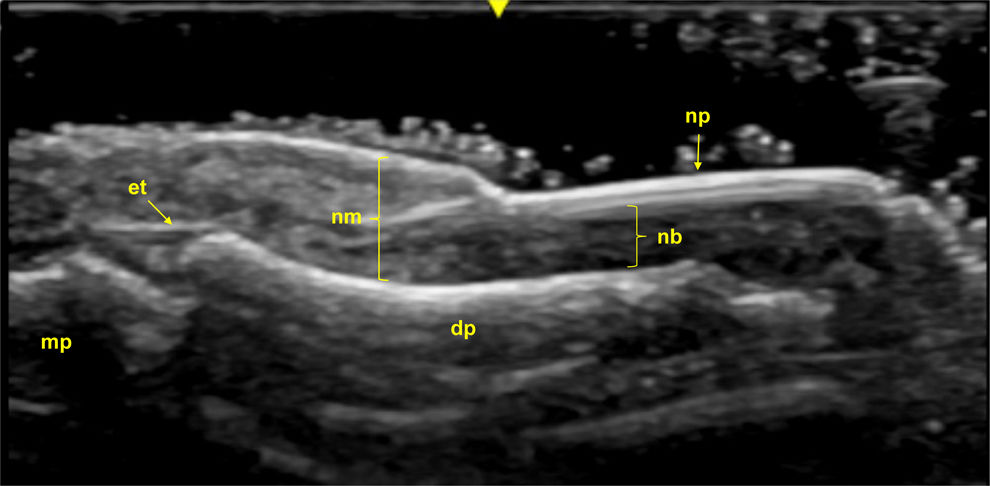

Ultrasound imaging identifies three primary structures of the nail apparatus: the nail plate, the nail bed, and the nail matrix. The nail plate consists of two parallel hyperechoic layers, separated by a hypoechoic interlaminar space, with normal thickness ranging between 0.3 and 0.65mm. The nail bed, a hypoechoic structure located between the ventral plate and the periosteum of the distal phalanx, measures between 0.7 and 6.5mm in thickness. The nail matrix, located proximally, appears isoechogenic and measures 1–5.3mm in length [134] (Fig. 5).

Fig. 5.Healthy Nail (Longitudinal View): Sonographic image obtained using Logiq e US system with an 8–18i MHz linear transducer. The nail plates (np) appear as two parallel hyperechoic layers, separated by a hypoechoic interlaminar space. The nail matrix (nm) is visible as an isoechogenic structure located proximally, while the nail bed (nb) is shown as a hypoechoic area between the ventral nail plate and the periosteum of the distal phalanx (dp). The extensor tendon (et) inserts distally at the base of the dp. mp=middle phalanx.

Ultrasonographic studies in psoriatic disease have shown significant increases in the thickness of the nail plate, bed, and matrix compared to healthy individuals, as well as compared to those with rheumatoid arthritis (RA) or osteoarthritis (OA). These alterations are present even in subclinical stages, highlighting its utility as a tool for early diagnosis and differential assessments in psoriatic nail disease [135,136].

Ultrasound is especially useful for detecting early psoriatic nail changes, such as minimal thickening of the nail bed or slight loosening of the ventral plate (Fig. 6). As the disease progresses, more pronounced alterations occur, including thickening of both the ventral and dorsal nail plates. In these advanced stages, the trilaminar structure of the nail plate, characteristic of healthy nails, is completely lost. The nail plate becomes thickened, wavy, and hyperechoic, with an inhomogeneous appearance [133,137] (Fig. 7). Power Doppler (PD) is particularly valuable for assessing inflammation in the nail matrix and bed, grading vascularization on a scale from 0 to 3, where higher values indicate greater inflammation [20].